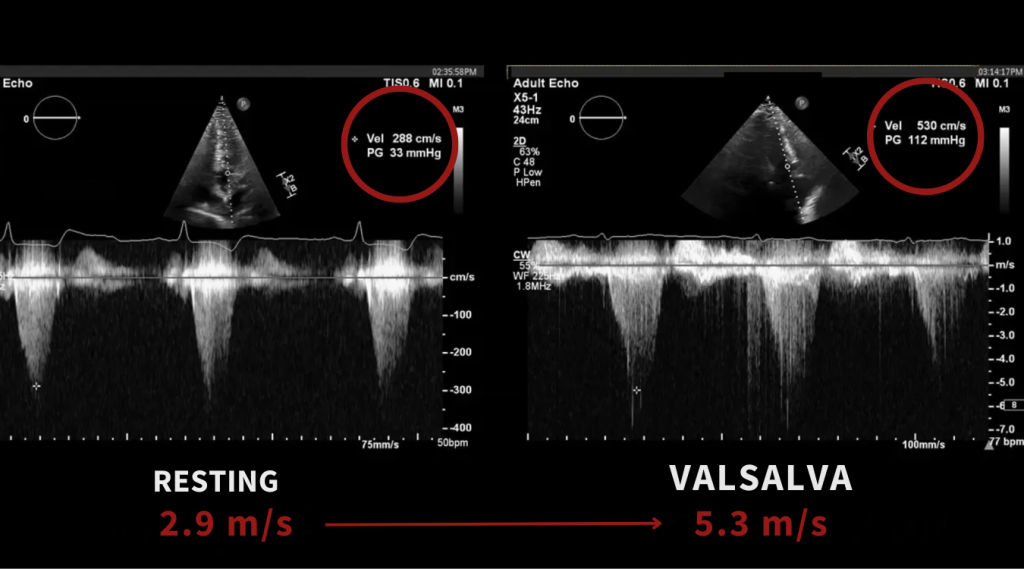

In some cases, a patient with a mild or absent gradient at rest may demonstrate a severe gradient with provocation.

When Is Obstruction Significant?

Once you’ve obtained the resting and provoked LVOT gradients, the next question is:

When does it become clinically significant?

In hypertrophic cardiomyopathy, an LVOT gradient ≥30 mmHg at rest or with provocation is widely used to identify obstructive physiology.

A gradient ≥50 mmHg at rest or with physiologic provocation is generally considered hemodynamically significant and is the threshold most often used to guide management decisions, particularly in symptomatic patients.

Key thresholds

- ≥30 mmHg = obstruction present

- ≥50 mmHg = clinically significant obstruction